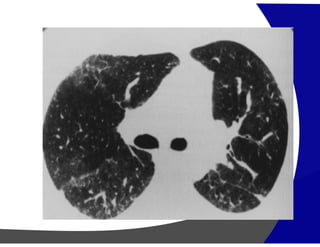

Opacidades Lineares irregulares

Opacidade Lineares Irregulares:

DDX:

• Fibrose pulmonar idiopática (FPI),

• Pneumonia de hipersensibilidade crônica (PH),

• Sarcoidose (Sar)

• Asbestose (Asb).

Distribuição:

Central – Sar e PH

Periferica – FPI e Asb